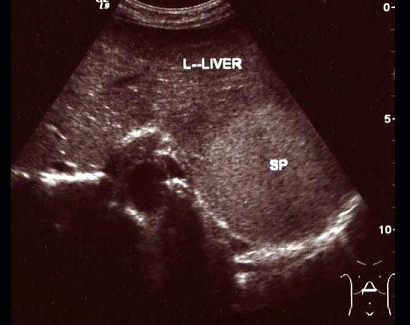

10、单项选择题

男、30岁,体检时发现脾门处光团,根据超声声像图诊断为()

A.副脾

B.淋巴结

C.转移癌

D.脾脓肿

E.左肾上腺肿瘤